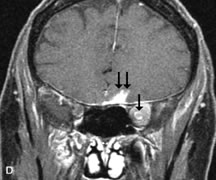

Contrast agents composed of paramagnetic or superparamagnetic materials can alter tissue properties to improve the MRI detection and characterization of certain pathologic lesions. Gadolinium diethylenetriaminepentaacetic acid (Gd-DTPA), the only paramagnetic agent currently approved in the United States for clinical applications, shortens the relaxation times of adjacent protons (hydrogen nuclei) and results in a bright signal on T1-weighted images. Gadolinium, like most heavy metals, is toxic in its nonchelated form but is safe when strongly bound to DTPA, which serves to eliminate its biologic toxicity. It is administered intravenously and is generally considered safer than iodinated radiographic contrast materials used for CT scans and arteriograms. It has little immunologic, systemic, and renal toxicity.20 Gd-DTPA has been shown to effectively detect disruption of the blood–brain barrier and delineate orbital tumors, such as meningiomas, gliomas, hemangiomas, and metastases (see Lacrimal Gland Tumors and Inflammatory and Lymphoproliferative Lesions in the section on Orbital Diseases). It also appears promising in identifying areas of altered circulation due to inflammation, ischemia, soft tissue injury, and neoplasia.7,8,21,22